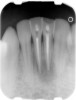

Class IC mandibular central incisors had extensive amounts of tooth structure remaining following endodontic treatment (Figure 12 and Figure 13). Restoration of the access holes was completed with bonded composite (Figure 14).

Figure 12  Endodontically treated mandibular central incisors that require only restoration of endodontic access holes with composite.

Figure 12

Figure 13  Access holes after endodontic treatment.

Figure 13

Figure 14  Final restoration with bonded composite.

Figure 14